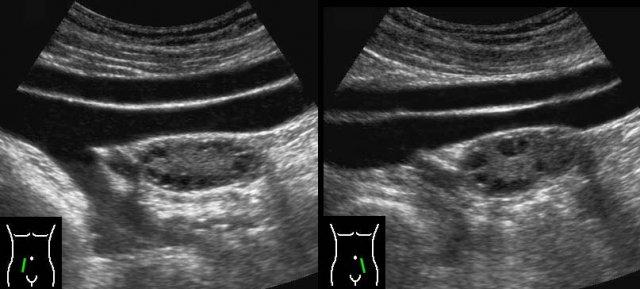

Ca lâm sàng 2

Ở người phụ nữ trẻ này với hai ngày đau hố chậu phải và CRP bằng 2, siêu âm phát hiện một nang buồng trứng bên phải thành mỏng.

Siêu âm đầu dò âm đạo (TVUS) cho thấy hình ảnh điển hình của các vách ngăn mỏng như ren, đồng thời thấy phần buồng trứng bình thường còn lại chứa các nang noãn bị “đẩy” sang một bên bởi nang xuất huyết.

Hình ảnh hoàn toàn bình thường sau 6 tuần.